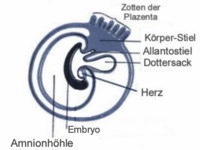

Sobald die Embryonen sich in der Gebärmutter eingenistet haben, beginnt die Ausbildung der Plazenta. Sie bildet am Ende einen gürtelförmigen Ring um den Keimling, der nun eine bohnenförmige

Gestalt angenommen hat. Jeder Embryo hat nun seinen festen Platz und einen eigenen Blutkreislauf. Manchen Hündinnen ist um diese Zeit schlecht und sie fressen nicht, denn die

Die Ausbildung der Plazenta ist nun abgeschlossen. Der Embryo hängt an der Nabelschnur wie ein Raumfahrer im Weltraum und bewegt sich frei in einer doppelten Fruchtwasserblase. Er ist dadurch

äußerst stoßgesichert. In den nächsten Wochen macht der Keimling die gesamte Entwicklungsgeschichte von der Urzelle bis zum Welpen durch, gut geschützt in den Uterushörnern und völlig isoliert

von den anderen Embryonen in den einzelnen Fruchtkammern. Am Ende dieser Embryonalperiode sind beim Hund alle wichtigen Organsysteme angelegt, die endgültige Körperform ist bereits in ihren

Grundzügen erkennbar. Man spricht nicht mehr vom Embryo, sondern vom Fötus. Sterben die Fruchtanlagen bis zum 28. Trächtigkeitstag ab, werden sie meist unauffällig resorbiert. Bis zur

Ab dem 22. Tag sind die Embryonen beim Ultraschall sichtbar und der Herzschlag kann zur Diagnose herangezogen werden. In dieser Zeit sind sie stark defektgefährdet, weil die Nervenstränge im Rückenmark gebildet werden und die Organe sich langsam entwickeln. Die Kleinen sind etwa walnussgroß.

Der Fötus durchläuft besonders am 31. / 32. Tag noch mal eine spannende und heikle Entwicklung. Es kommt zum so genannten Nabelbruch, d.h. der Darm wird kurzzeitig aus der Körperhöhle verlagert um schneller wachsen zu Bis zum 33. Tag wachsen die Fruchtampullen zusammen. Zunächst zeigt die Gebärmutter oviole Fruchtampullen , die um den 33. bis 35. Tag „zusammenfließen“ und zu Schläuchen auswachsen. Die Gebärmutter faltet sich, da der Platzbedarf der Welpen enorm ist.

In der 5. Woche steigt das Gewicht stetig an, die Feten beginnen sich zu drehen und die Hündin zieht ihre Beine nicht mehr gerne an. Die Fetalperiode ist durch die Ausdifferenzierung der Organe und das schnelle Wachstum der Welpen gekennzeichnet. Die Augenlider sind ausgebildet, die Ohrmuschel bedeckt den Gehörgang, die Finger separieren sich, das männliche Genital ist erkennbar und die fünf Zitzenpaare ebenso. Die Föten sehen nun aus wie kleine Hunde, Kopf und Rumpf sind unterscheidbar. Auch die Fellfarbe beginnt sich in diesem frühen Stadium zu entwickeln. Die Barthaare und Krallen wachsen jetzt auch. Mit dem Stetoskop sind die Herztöne nun hörbar, beim Ultraschall sind sie nicht mehr zu identifizieren aufgrund der ansteigenden Flüssigkeit. Die Hündin nimmt an Bauchumfang zu. Die Zitzen schwellen an und werden dunkler.